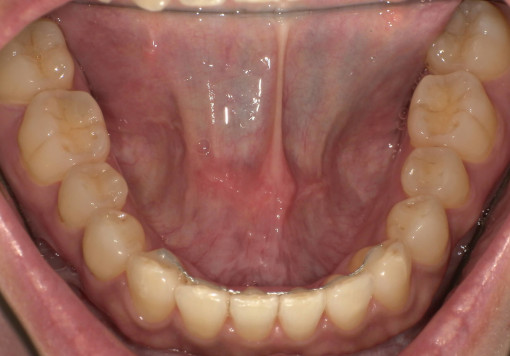

before

after

- 主訴:歯並びが気になる

- 治療内容:下顎のみマウスピース矯正

- 治療期間:1年間6ヶ月

- 診断結果:歯列不正

- 治療後経過:経過良好

- 治療費用:40万円

リスク・副作用:歯肉退縮、歯の動揺、歯根吸収